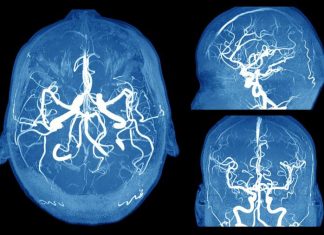

6 Scary Signs of a Brain Aneurysm Everyone Should Know

A brain aneurysm is a bulge in a blood vessel in the brain, according to the Mayo Clinic. It’s been described as looking like...